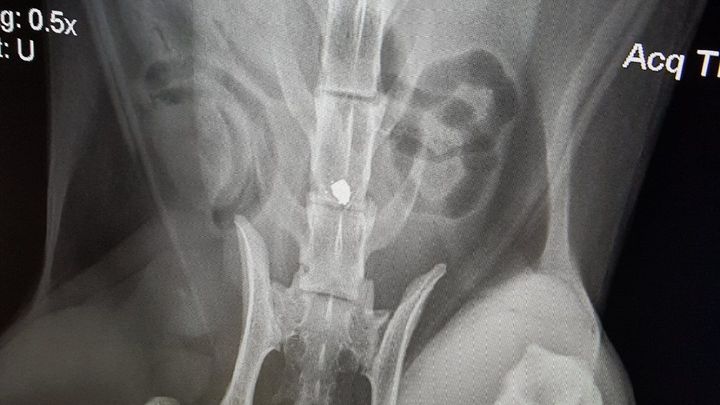

This morning on March 16th, their beautiful, sweet kitties were attacked in Santa Rosa. Carson, the brown striped little guy was shot with a BB gun in his back leaving him paralyzed. Frenchie, the black and white tuxedo kitty had a huge gouge in his foot that was so deep it showed the bone.

They are both at the emergency vet now. Carson's recovery does not look good and the surgery to possibly give him a fighting chance is very expensive. As of right now, he will require to be hand fed and cleaned and will have no use of his lower half. Frenchie will require stitches.